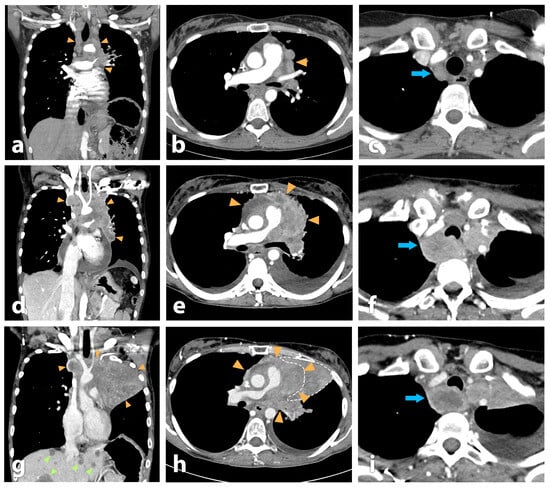

Objectives: Peptide receptor radionuclide therapy (PRRT) of neuroendocrine tumors (NETs) commonly relies on somatostatin receptor subtype 2 (SSTR2) agonists such as DOTA-TOC/TATE, which may show limited efficacy due to high hepatic uptake and therapy resistance in some patients. SSTR2 antagonists have demonstrated [...] Read more.

Objectives: Peptide receptor radionuclide therapy (PRRT) of neuroendocrine tumors (NETs) commonly relies on somatostatin receptor subtype 2 (SSTR2) agonists such as DOTA-TOC/TATE, which may show limited efficacy due to high hepatic uptake and therapy resistance in some patients. SSTR2 antagonists have demonstrated superior tumor targeting. This study aimed to establish the production and quality control of the Actinium-225-labeled SSTR2 antagonist [225Ac]Ac-DOTA-LM3 and to report in-human clinical experience with targeted alpha therapy (TAT). Methods: [225Ac]Ac-DOTA-LM3 was produced by radiolabeling DOTA-LM3 with Actinium-225 under validated conditions. Radiochemical conversion, purity, yield, and stability were assessed using radio-TLC, fractionated radio-HPLC combined with gamma spectroscopy, and in vitro serum stability testing. Clinical feasibility and therapeutic response were evaluated in a patient with metastatic neuroendocrine pancreatic neoplasm refractory to prior 177Lu-based PRRT. Results: Radiolabeling achieved reproducibly high radiochemical purity (>97%) and decay-corrected yields exceeding 80%. The radiopharmaceutical showed high in vitro stability with minimal release of free Actinium-225 over five days. Fractionated radio-HPLC enabled indirect purity assessment. In the reported patient, [225Ac]Ac-DOTA-LM3 therapy resulted in partial remission without clinically relevant hematologic, renal, or hepatic toxicity and was associated with marked clinical improvement. Conclusions: [225Ac]Ac-DOTA-LM3 can be produced with high purity and stability using clinically applicable procedures. In-human results suggest promising efficacy and safety, supporting further clinical investigation of Actinium-225-labeled SSTR2 antagonists for advanced NETs. Full article

Show Figures

Figure 1